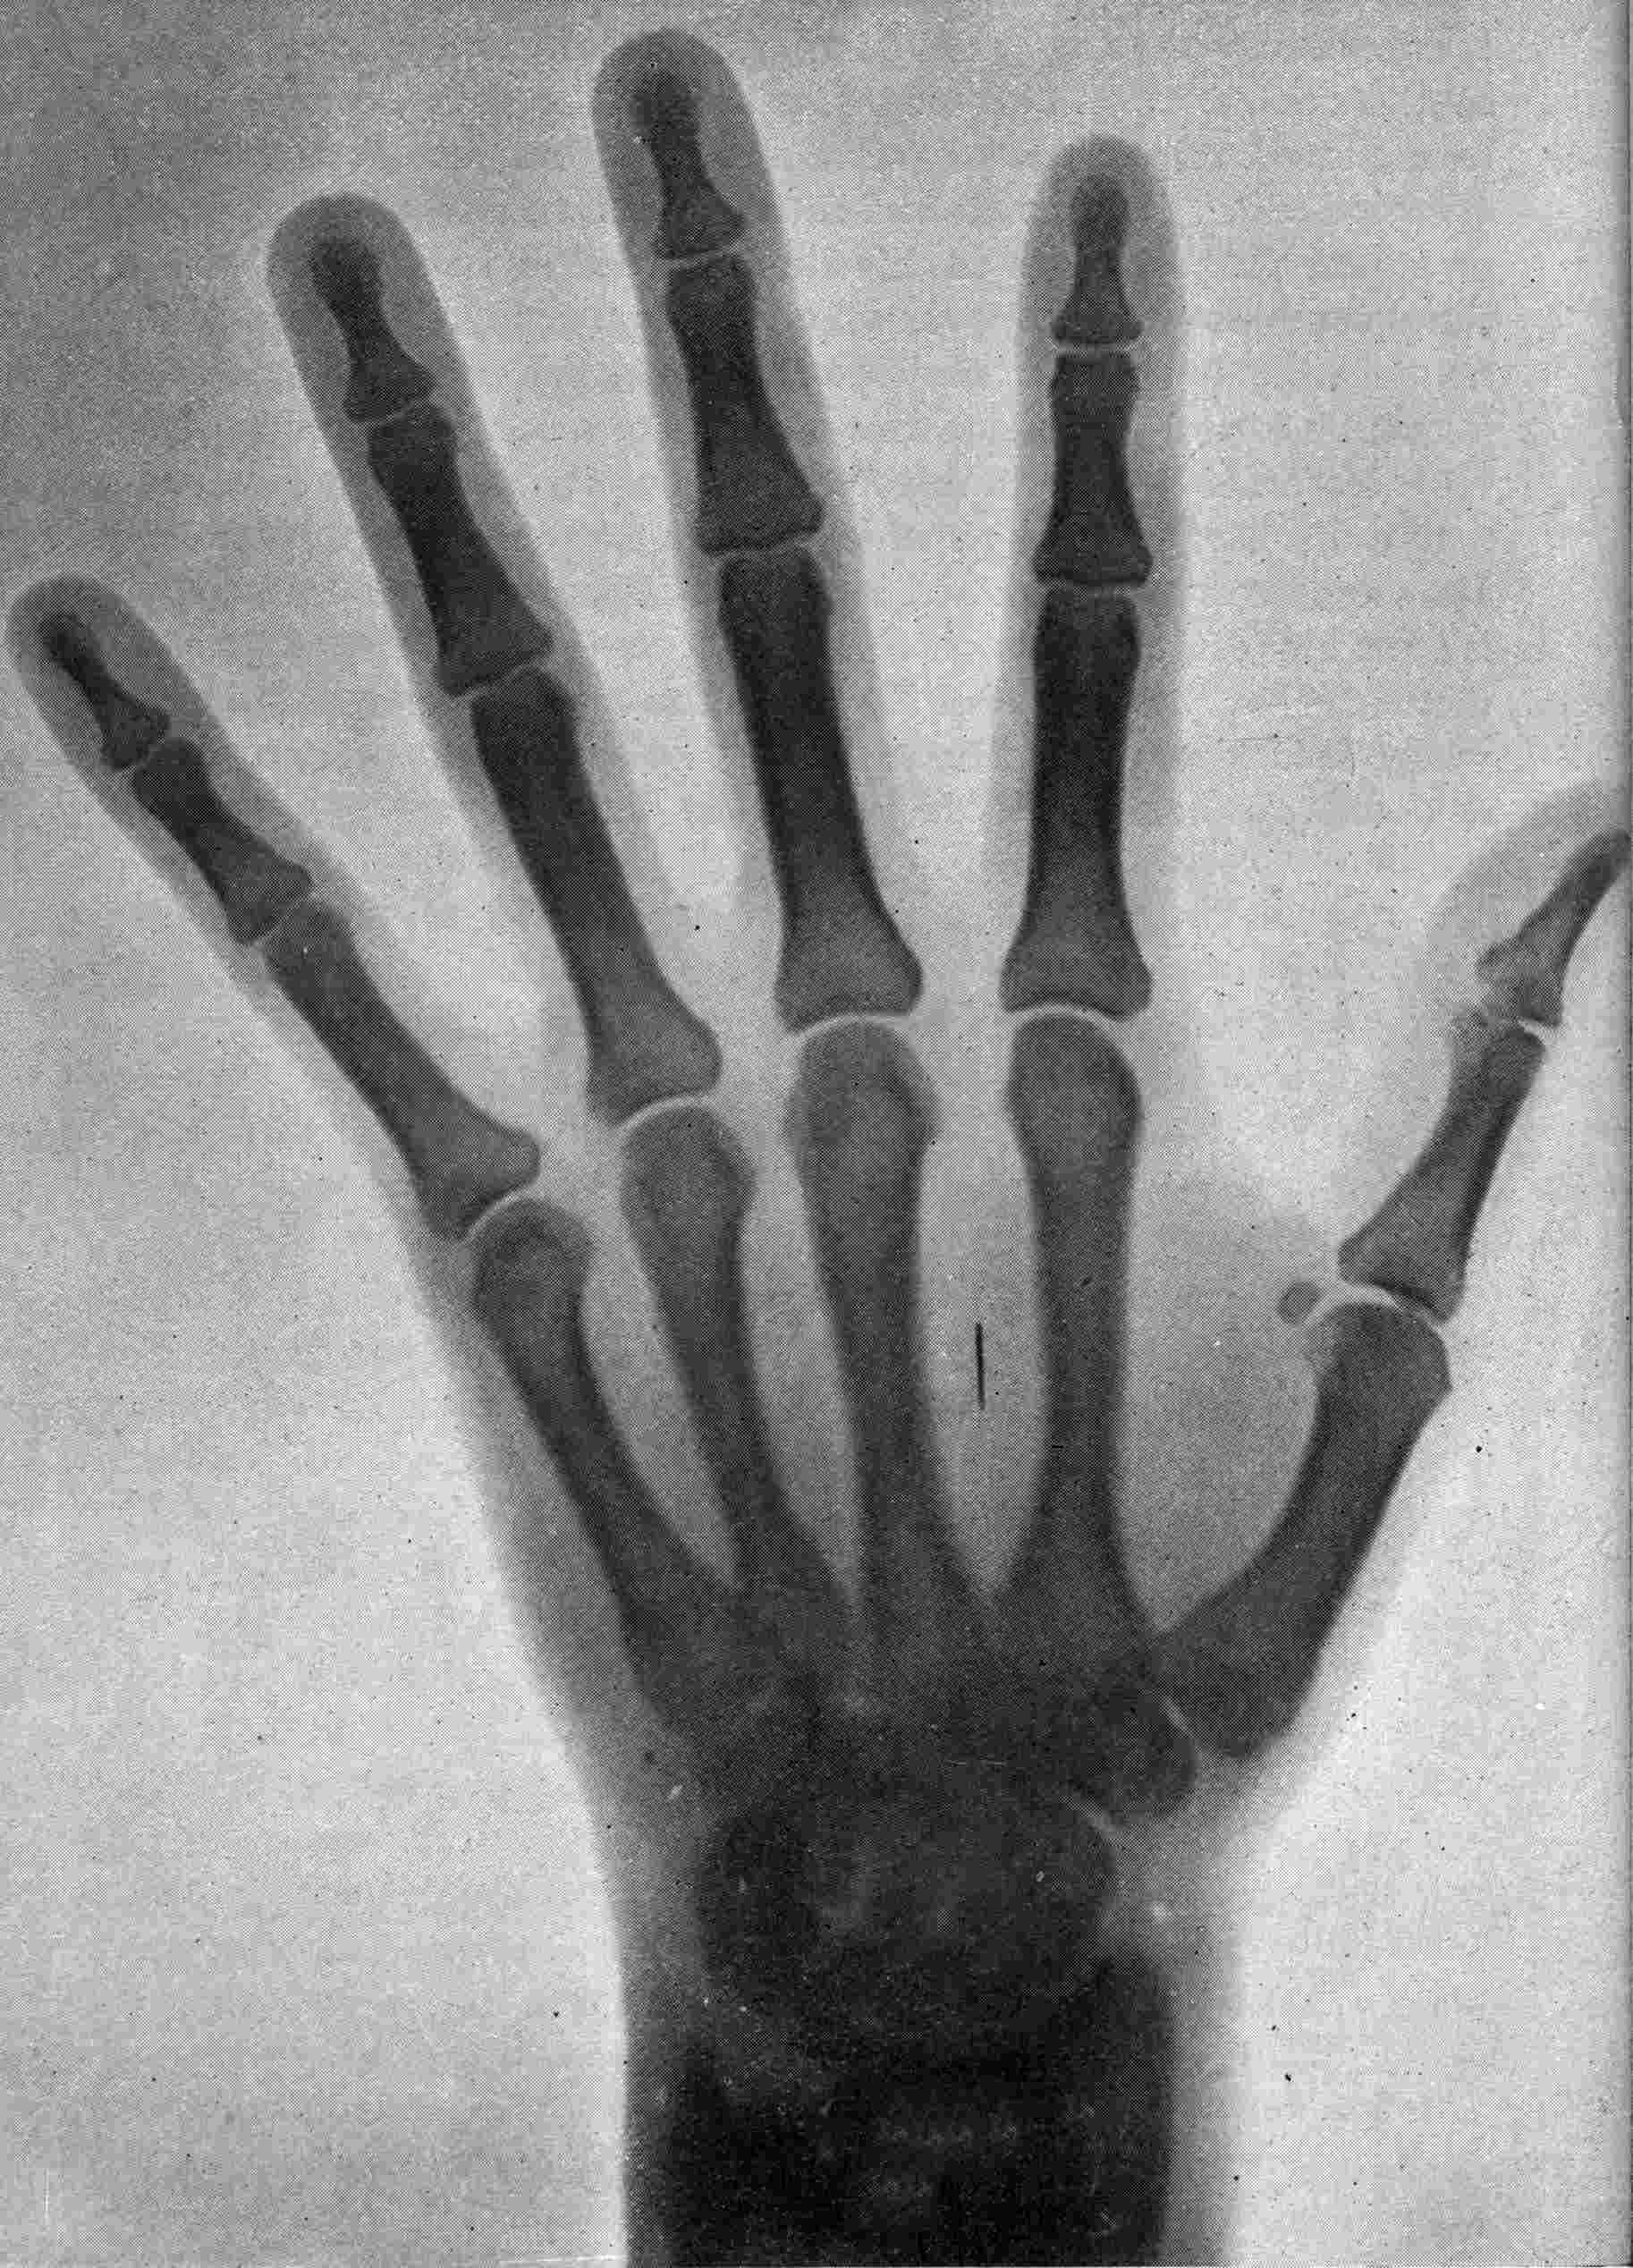

Fig. 2.—Broken Arm, Overlapping.

FROM SCIAGRAPHS BY PROF. DAYTON C. MILLER. § 204.